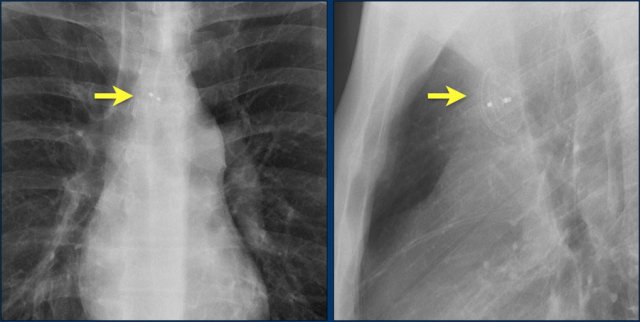

Subtle lead fracture in malfunctioning pacemaker.

Extremely subtle fracture line (arrow).